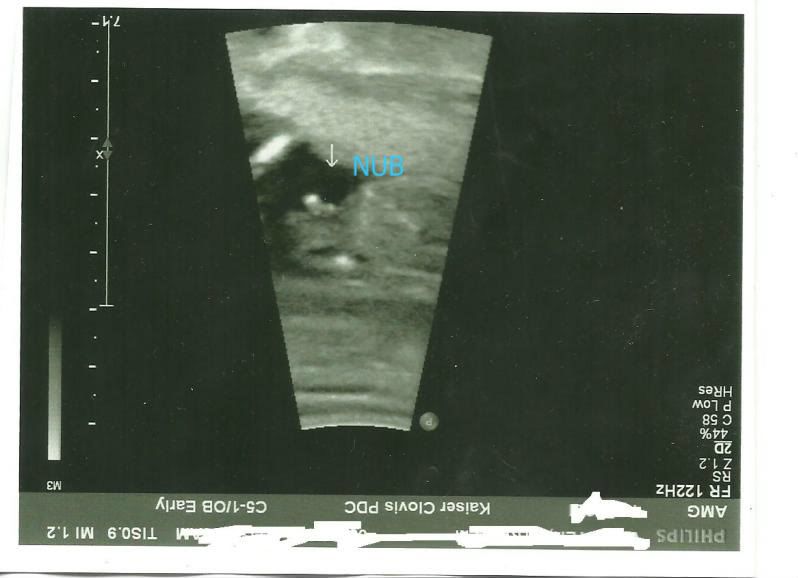

I don't see many people on here that know about the "nub theory" I found this site called ingender.com when I was pregnant with my last son and its pretty awesome. At my NT scan they looked at the "nub" and if its flat it's a girl and 30 degrees or higher angle its a boy. The site has a whole section dedicated to it you can even post up your NT scan pics (as long as its a profile shot with the nub showing) the ladies on there are pretty good at guesing. I have been at it for almost 2 years so if you have a nt scan pic and I can even look and see if the nub is showing and can give you a good idea what it is. My NT scan for #3 is on the 17th I hope I have the same tech because she was 100% right last time.

They told me boy...what do you think?

yes --here it is same pic less blury

and even though in the pic your babies spine is curved up some the nub is almost at a 90 degree angle both of my boys were that way.